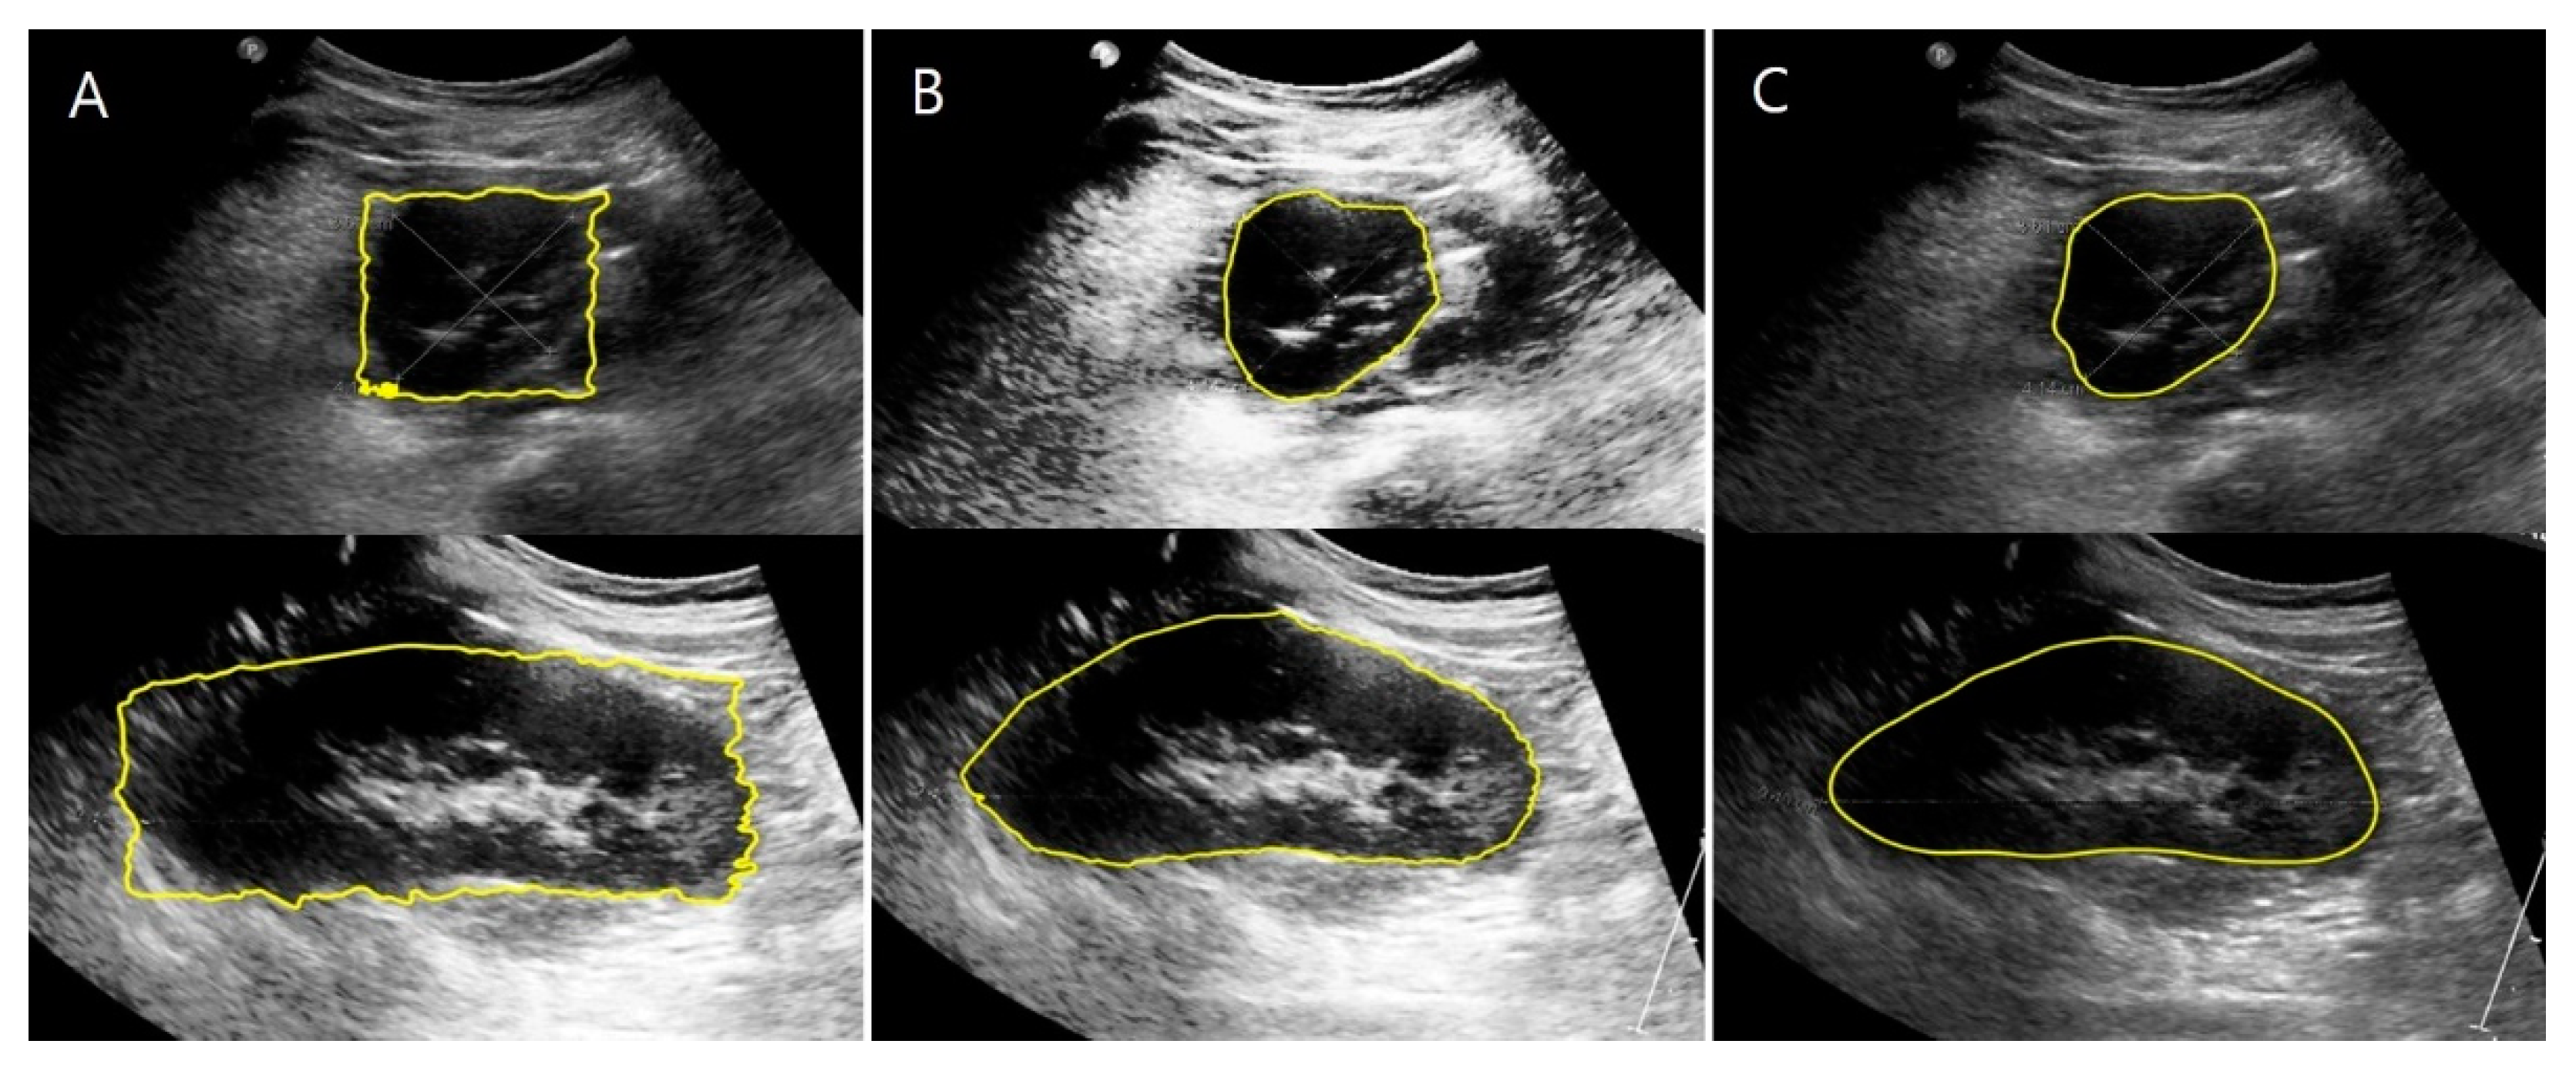

2.3.2. US Images and Image Processing Program